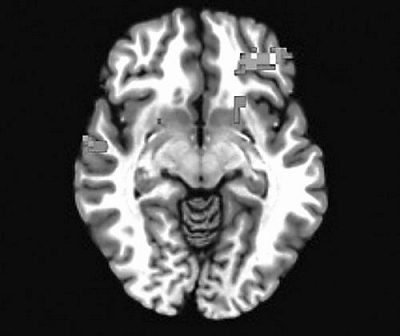

当青少年在一项常规的冲动测试中成功抵制冲动时,他们的大脑中负责约束管制的区域会明显表现得更加活跃。图片来源:神经科学协会

研究小组称,青少年相比成年人和儿童在同样面对具有威胁性的面孔时表现出冲动的比例要高出大约15%。男性表现得要比女性差,这与男女青少年犯罪不成比例的事实相符合,体现了性别上的差异,Caudle说。那些设法抑制自己的青少年在大脑一定区域的活动表现明显活跃,这一区域被称为腹内侧前额叶皮质(vmPFC),该区域参与人类自上而下的控制行为。